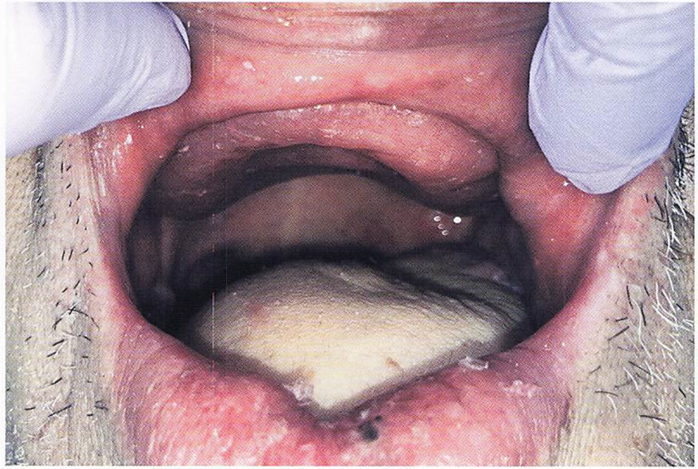

76歳の男性。2日前に脳梗塞を発症し、急性期病棟に入院中である。口腔清掃が自立していないため、主治医から歯科に口腔衛生管理の依頼があった。 挺舌時の口腔内写真を別に示す。 舌の異常所見はどれか。1つ選べ。

a.萎縮